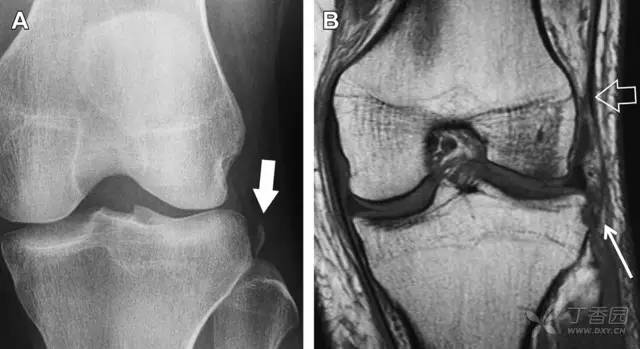

胫骨平台内侧皮质骨撕脱性骨折,被称为内侧 Segond 骨折或反向 Segond 骨折(图 5)。这种骨折的旋转机制与 Segond 骨折相反,该骨折与后交叉韧带断裂及内侧半月板损伤相关。

图 5 一位足球运动员的反向 Segond 骨折

A 正位片示关节线处的胫骨内侧见一细小骨折片(箭头)。B MRI 冠状位 T1 加权像示骨折片出现在内侧副韧带关节囊附着处(方框)。